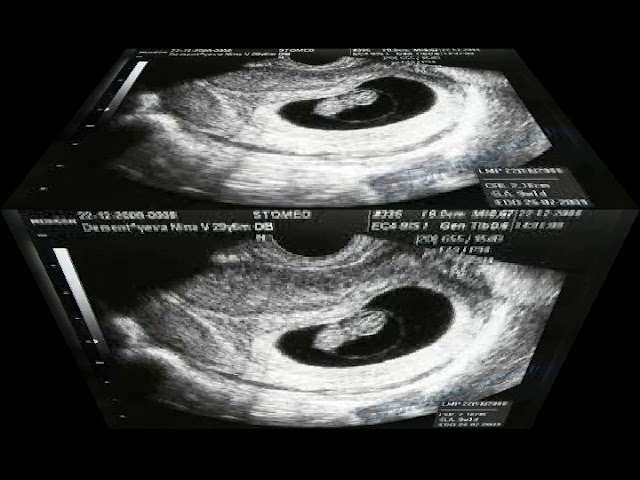

Беременность 6 недель может стать поводом для УЗИ, только если врач предполагает, что она многоплодная, либо у женщины были в анамнезе выкидыши и случаи внематочной беременности. В обычной ситуации в проведении ультразвукового обследования сейчас нет необходимости.

УЗИ обычно проводят трансвагинальным датчиком – на этом сроке данный способ более информативен. Будущая мама сможет услышать, как бьется сердечко ее малыша, увидеть его на экране монитора и на фото.

Врач делает выводы о расположении плодного яйца, его размерах и точном сроке беременности.

На данном сроке гинеколог, который ведет беременность, нередко отправляет будущую маму на ультразвуковую диагностику. УЗИ, которое делают на 6 неделе беременности, как правило, требуется не для установления самого факта зачатия. На таком сроке это можно определить при обычном гинекологическом осмотре. Основная его цель – выявить возможные патологии.

3. На 6 неделе с помощью ультразвукового исследования уже можно определить жизнеспособность плода. Врач выносит заключение исходя из размеров эмбриона, частоты сердечных сокращений, его двигательной активности. Однако из-за раннего срока, при любом диагнозе лучше пройти еще одно обследование у другого специалиста, чтобы исключить возможность ошибки.

4. Если беременность развивается как положено, врач во время процедуры определит точный срок зачатия, место имплантации эмбриона (идеальной считается задняя стенка матки), наличие многоплодной беременности. В последнем случае специалист также должен сказать, является ли беременность однояйцевой или многояйцевой — это важно для дальнейшего наблюдения и родов.

В 6 недель беременности размер плода позволяет увидеть на фотографии УЗИ крохотные ручки и ножки. Они уже сгибаются и разгибаются, а на мониторе аппарата можно проследить за движениями малыша. Определить пол ребенка еще не представляется возможным, так как половые органы только начали свое развитие, зато уже можно рассмотреть формирующиеся глазки и кончик носика.

Врач также должен оценить правильность развития сердца плода, прослушать его биение. На таком сроке нормой является ЧСС 150 ударов в минуту.